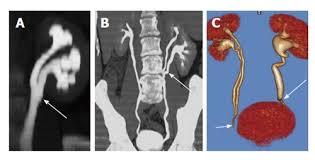

28 Year Old Woman With Duplex Collecting System In A Pelvic Kidney Download Scientific Diagram